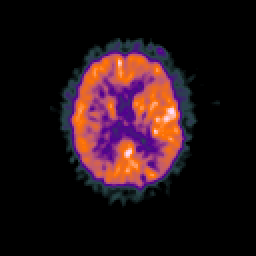

Glioma overlay -- Slice #69

[Home][Help][Clinical] Slice 69